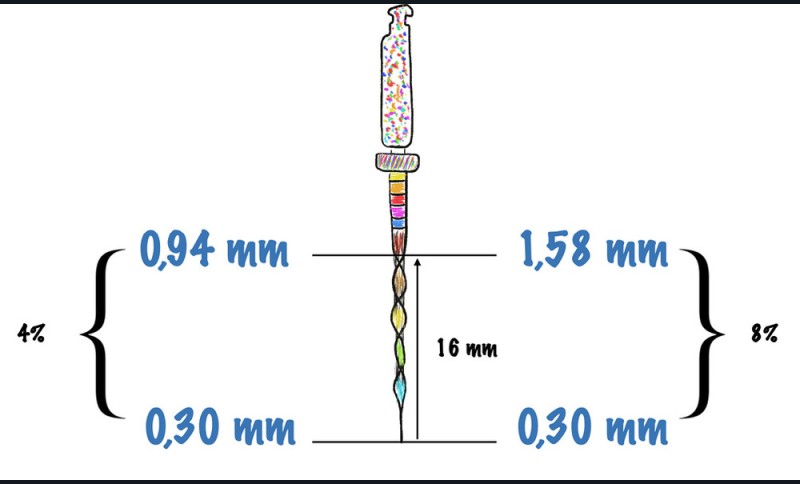

La largeur de travail

La largeur de travail, ou diamètre apical de préparation, correspond à la largeur à laquelle le diamètre apical initial sera préparé, afin de permettre un nettoyage et une désinfection les plus complets possible du tiers apical.

Une largeur de travail trop petite

Trop petite (fig. 7), elle ne permettra pas un nettoyage instrumental ni une désinfection correcte (apport de l’irrigant jusqu’à l’apex insuffisant). Il en résultera un risque majoré d’infection secondaire en raison de la présence potentielle de bactéries intra-canalaire et/ou dans la dentine radiculaire.

Une largeur de travail trop large

Celle-ci présente un risque iatrogénique non négligeable (butée, fausse route, perforation, zipping, stripping) [12] et une préparation invasive de dentine saine (fig. 7). La désinfection ne s’en trouve pas significativement améliorée par rapport à une largeur de travail correctement choisie [13].

Une largeur de travail aussi petite que possible, aussi large que nécessaire

Cette largeur de travail (fig. 7) est en adéquation avec l’anatomie apicale [14], non-iatrogénique, autorisant un nettoyage et une désinfection correcte, en adéquation avec les sensations cliniques du praticien et des résultats cliniques prouvés [15]. Cette valeur du diamètre apical idéal fait encore débat dans la littérature, et oscille entre 30 et 50/100e mm en fonction de la situation clinique (fig. 8).

La conicité

La conicité peut être définie par l’augmentation de la largeur ou du diamètre d’un objet en fonction d’une certaine distance. Par exemple, une lime 15/100e mm présente une conicité de 2 %. En partant de l’extrémité apicale de la lime, le diamètre augmente de 0,02 mm par millimètre.

Une conicité trop faible

Si elle préserve au maximum la biomécanique de la dent, une conicité trop faible (fig. 9) peut compromettre le pronostic endodontique, avec un nettoyage instrumental insuffisant, une désinfection incomplète (par manque de volume canalaire disponible pour l’irrigant), une obturation potentiellement difficile à réaliser et pouvant ne pas jouer son rôle de remplissage tridimensionnel.

Une conicité trop importante

Si elle optimise le pronostic endodontique, une conicité trop importante (fig. 9) pourrait compromettre le pronostic biomécanique par un travail trop important de la dentine péricervicale, pouvant entraîner un stripping, voire une perforation dans certaines zones à risque (par exemple la paroi disto-linguale de la racine mésio-vestibulaire (MV) d’une première molaire mandibulaire).

Une conicité aussi petite que possible, aussi large que nécessaire

Il s’agit d’une conicité qui optimiserait les pronostics à la fois biomécanique et endodontique (fig. 9). Cette valeur de la conicité idéale fait encore débat dans la littérature, et oscillerait entre 4 et 6 % [16, 17].